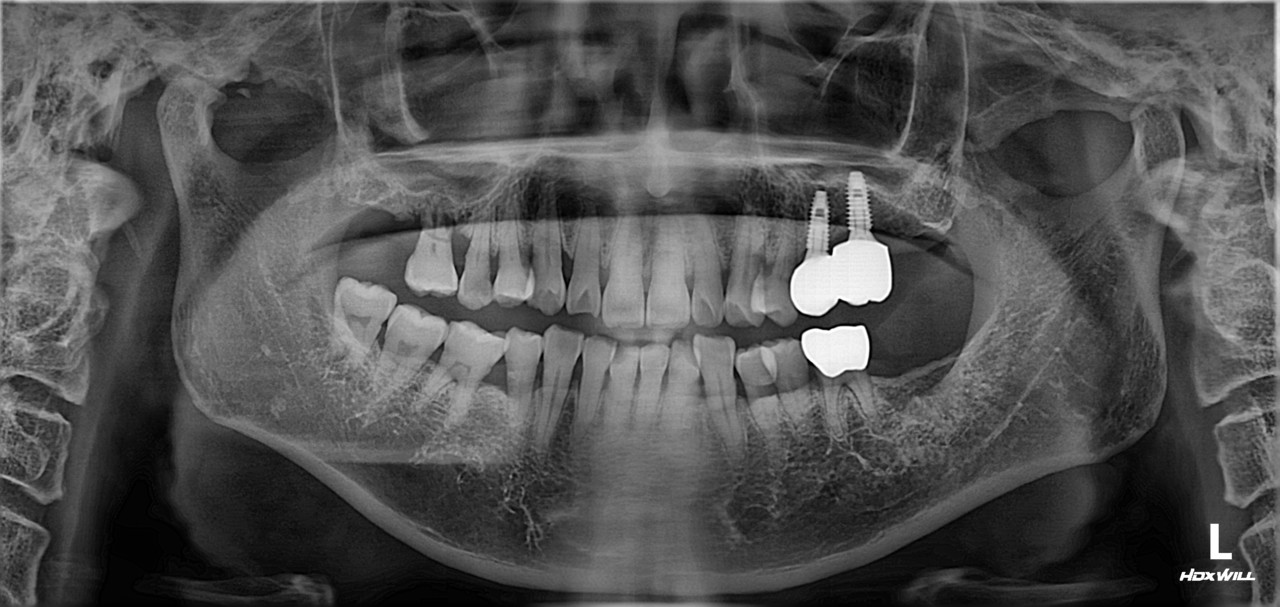

상악동 거상술 및 임플란트 식립

치료 기간 2023. 12. 21(치료 당일)

아래 치료는 상악동 거상술 및 임플란트 식립에 대한

치료 당일에 대한 설명입니다.

우측 상악 잔존골이 얼마 없는 난이도가 있는 수술이지만, 참조은치과에서는 수술시간이 15분 정도 소요되었습니다. 근육주사를 이용하여 붓기 조절 및 염증 조절도 시행하였습니다.

아래 치료는 상악동 거상술 및 임플란트 식립에 대한 치료 당일에 대한 설명입니다.

우측 상악 잔존골이 얼마 없는 난이도가 있는 수술이지만, 참조은치과에서는 수술시간이 15분 정도 소요되었습니다.

근육주사를 이용하여 붓기 조절 및 염증 조절도 시행하였습니다.